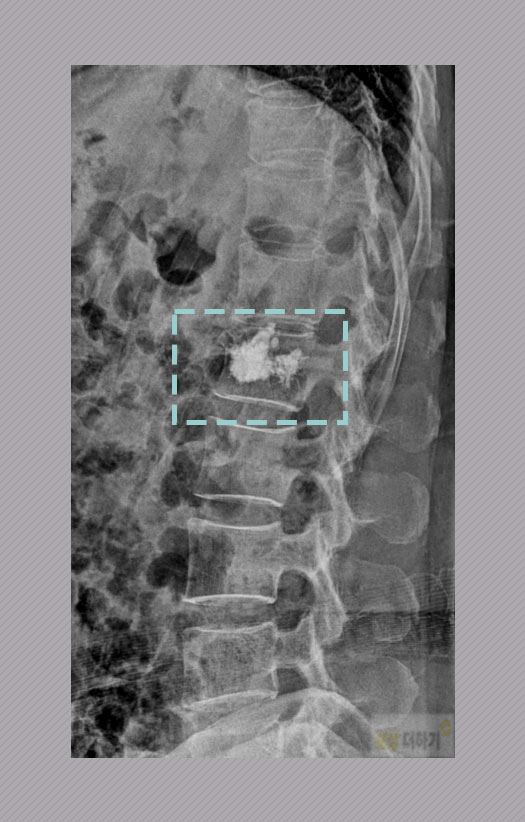

▶ 진단 및 치료 제1요추 압박 골절 S32.020 엑스레이, MRI 검사를 모두 하여 허리 즉 요추 1번 부상이 확인되었습니다. 같은 진단이라고 해도 그 형태나 통증의 정도, 나이와 신체 상태 등에 따라 어떤 치료를 선택할지 모두 다른데요. A 님은 골다공증이 있는 분으로 보존적 요법을 적용했지만 회복이 안되어 경피적 척추 시멘트 성형술을 받으셨습니다.

허리 압박 골절 (요추 1번) 후유장해 기준 - 비수술 -

▶ 보험약관 후유장해 기준 허리 압박 골절 (비수술) 보조기 착용, 약물 치료, 성형술 하신 경우 압박률 또는 척추의 전만증, 후만증, 측만증 변형이 있는지에 따라 기형 장해로 판단을 합니다. * 압박률: 찌그러진 추체의 높이를 측정(백분율 산정) * 전만, 후만, 측만증: 척추가 휘어지는 증상, 몇 도인지 측정